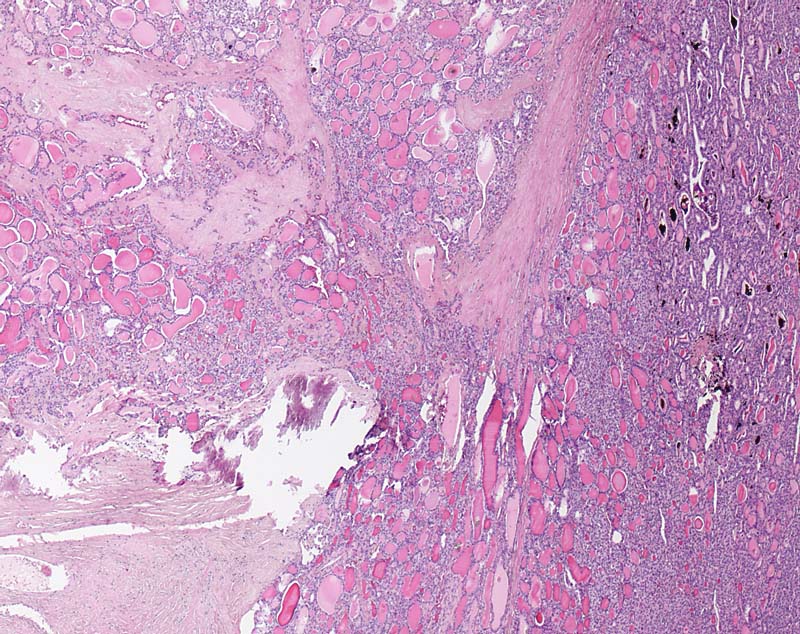

Grob invasives follikuläres Schilddrüsenkarzinom

Der follikuläre Tumor durchbricht die dicke bindegewebige Kapsel und infiltriert breitflächig das angrenzende Gewebe (links im Bild).

Kapseldurchbrüche mit ausgedehnter Invasion des benachbarten Gewebes fanden sich an zahlreichen Stellen. Somit handelt es sich um ein grob invasives follikuläres Karzinom.